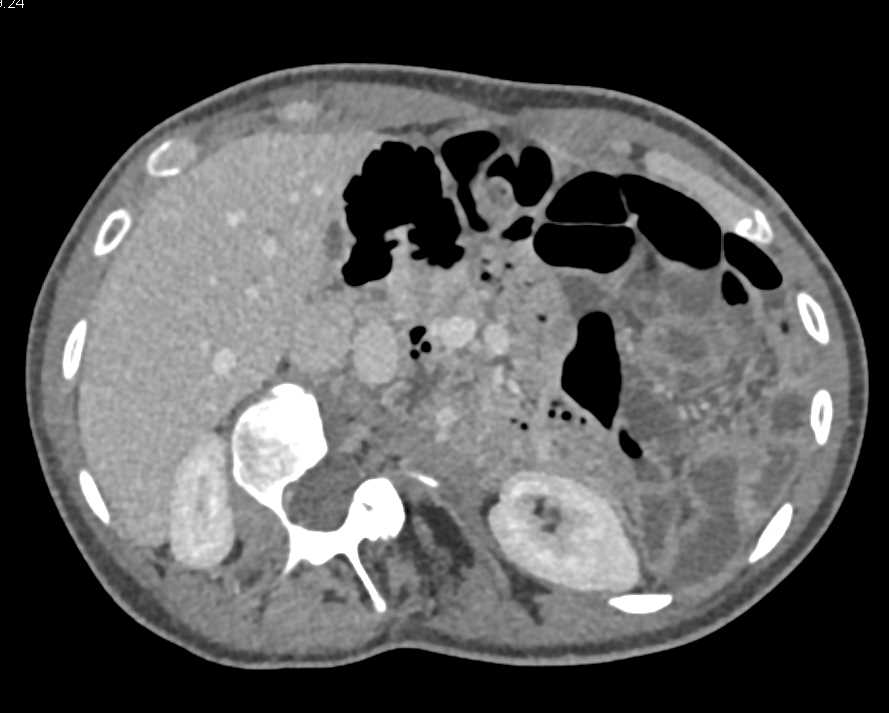

Neuroendocrine Tumor with Superior Mesenteric Vein (SMV) Occlusion